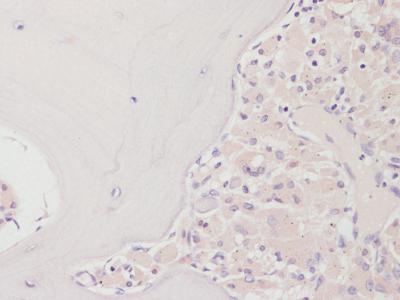

The findings, published today (Monday 11 January 2021) in the journal The Lancet Rheumatology , show that the treatment kills around 90 per cent of the cells responsible for bone loss in patients due to have revision hip surgery who were treated with denosumab. A total of 22 patients took part in the Phase 2 clinical trial sponsored by Sheffield Teaching Hospitals and funded by Amgen, Inc.

Professor Wilkinson, who is an Honorary Consultant Orthopaedic Surgeon at Sheffield Teaching Hospitals Foundation Trust, said: "It is very clear from our bone biopsies and bone imaging that the injection stops the bone absorbing the micro-plastic particles from the replacement joint and therefore could prevent the bone from being eaten away and the need for revision surgery.